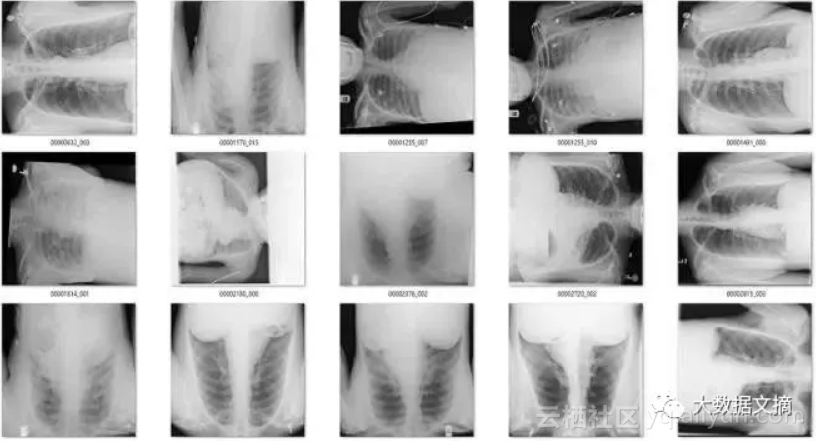

该模型一共标记出了171个“旋转”的图像。有趣的是,它实际上作为一个“异常”检测器,识别出许多在非胸部X光的图像。这也不难理解,因为这个模型可能是在学习解剖学的标志。任何异常的东西,如旋转的图像或者是其他身体部位的X射线图像,都不具有正常图片应有的特征。真是意外收获!

在余下的120个图像中,56个并不是正面胸片。其中主要包括了侧面胸片和腹部X光片,这也是我想要清理出去的异常图片。

即使是很少量的带标签的数据都很有帮助。我用旋转检测器检测到的侧面和错误区域的X光图(n=56张)训练了一个新的模型。

结果很好!新的模型帮我找到了几百张侧面,腹部和骨盆X光图。

显然,如果我从头开始创建这个数据集,我需要找到很多非前胸X光图,其实也不难,这样的图片我有的是。